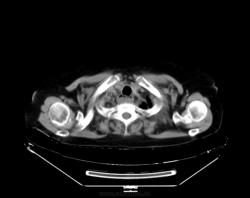

При профилактическом исследовании у женщины 75 лет выявлены изменения в легких и средостенье. Выполнена КТ. Ваше мнение, коллеги?

На сколько я понимаю это пищевод с содержимым, вот только не понятно на последнем скане, режим бы другой.

Но там была ахалазия. А по рентгенограммам, мне, что-то кажется, что в данном случае аорта.

Почему провокация?! У меня что, имидж такой? о провокациях я так сразу и пишу в заголовке... Нет здесь ни провокации, ни загадки. Действительно, ахалазия кардии, пневмофиброз в легких, по-видимому метатуберкулезный. А случай мне показался интересным, потому как эта ахалазия имеет 50 лет анамнеза без лечения